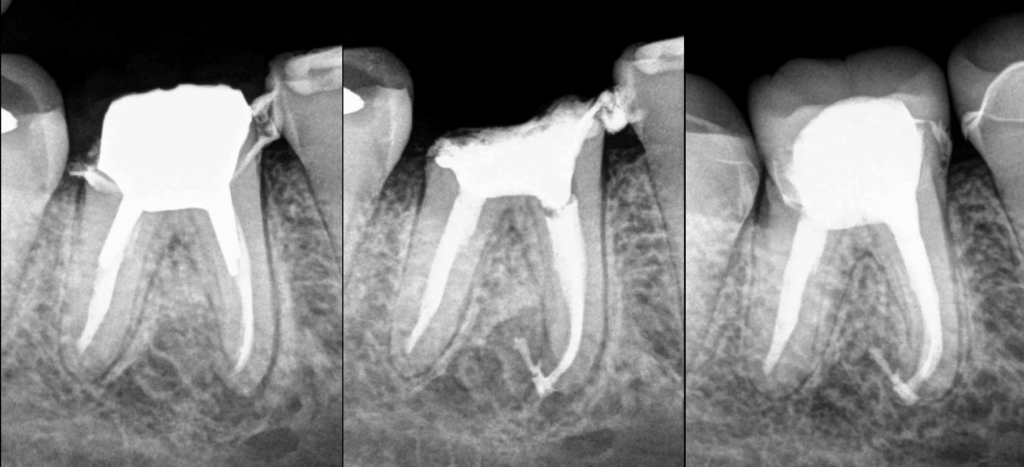

🔍 𝐃𝐞𝐧𝐭 𝟒𝟔

🦷 𝐏𝐮𝐥𝐩𝐞 𝐩𝐫𝐞́𝐜𝐞́𝐝𝐞𝐦𝐦𝐞𝐧𝐭 𝐭𝐫𝐚𝐢𝐭𝐞́𝐞

⚠️ 𝐏𝐚𝐫𝐨𝐝𝐨𝐧𝐭𝐢𝐭𝐞 𝐚𝐩𝐢𝐜𝐚𝐥𝐞 𝐚𝐢𝐠𝐮𝐞̈ (lésions apicales M et D)